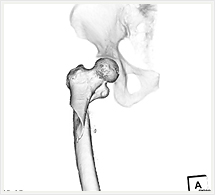

画像紹介

CTでは輪切り像の他にも立体的な画像(3D画像)を作成することもできます。そのためにはより細かくキレイな画像を撮影しなければなりません。当院では64列CTを導入しており、キレイな画像をより細かく撮影することができます。その画像を元に3D画像を作成することによって、より正確な手術のシミュレーションが可能になります。実際に手術をしたときの様子が、手術をする前に画像として見らます。外科系の手術には欠かせない技術となっておりますが、内科系でも血管内手術にも多く利用されております。

当診療放射線技術科では毎日各診療科に対して、その手術に最適な3D画像を提供しております。

以下にその3D画像を一部分紹介します。

四肢

(骨盤骨半透明)